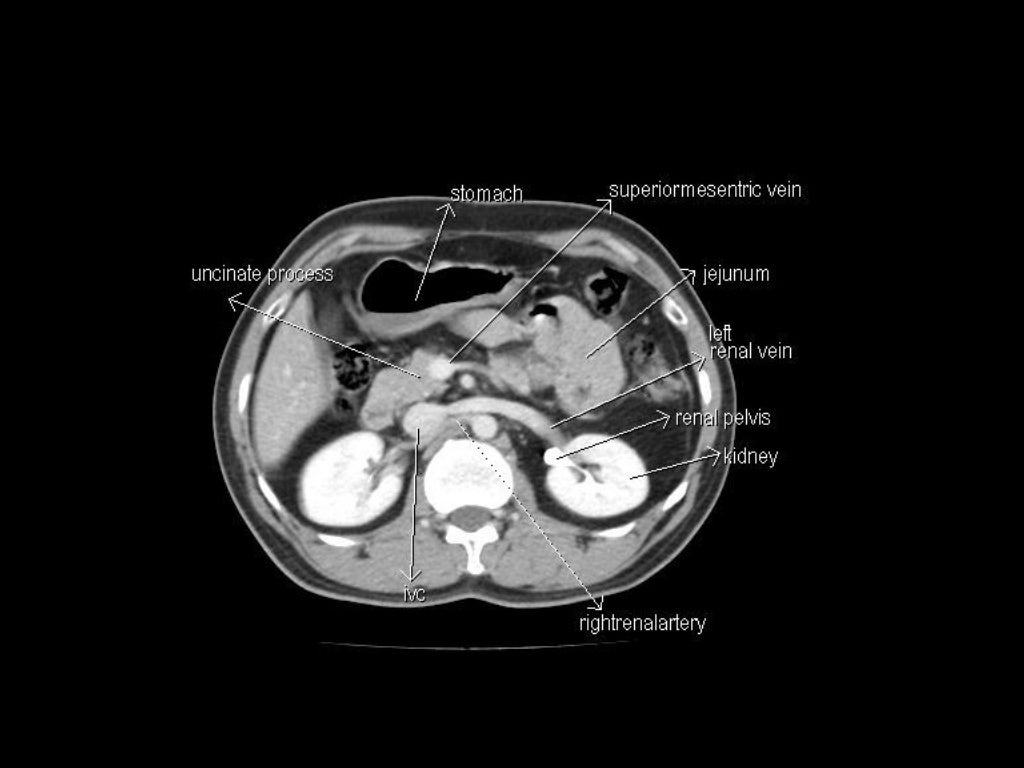

This article lists a series of labeled imaging anatomy cases by body region and modality. Brain CT head: non-contrast axial CT head: non-contrast coronal CT head: non-contrast sagittal CT head: non-contrast axial with clinical questions CT The data sets were designed to serve as (1) a reference for the study of human anatomy, (2) public-domain data for testing medical imaging algorithms, and (3) a test bed and model for the construction of network-accessible image libraries. The CT data consist of axial CT scans of the entire body taken at 1mm intervals at a pixel resolution

CT Scan Anatomy Overview. CT scans, or Computed Tomography scans, are essential tools in modern medicine. They provide detailed images of the inside of your body and are particularly useful for diagnosing conditions that affect the bone and soft tissues. Understanding CT scan anatomy is crucial for interpreting these images accurately.